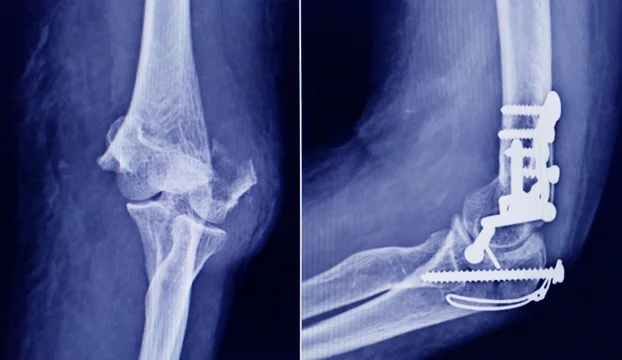

La Administración Nacional de Medicamentos, Alimentos y Tecnología Médica (ANMAT) advirtió a la población por un tornillo utilizado en cirugías traumatológicas debido a que es falso, por lo que su uso representa riesgo para la salud del paciente al que se lo implante.

Dicho tornillo es producido por la firma Stryker Corporation, que se encuentra registrada ante ANMAT bajo el PM 594-139. Luego de la inspección, se exhibió la muestra recolectada ante la responsable técnica de dicha empresa, quien afirmó que se trataba de un producto falsificado.

Las autoridades de la ANMAT dieron a conocer las características del producto para su advertencia: STRYKER 10 mm X 28 mm – BIOABSORBABLE – ACL INTERFERENCE SCREW – REF 234-010-067 – LOT 90905.